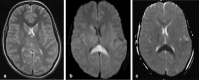

Background and purpose: The splenium of the corpus callosum is the most posterior part of the corpus callosum. Its embryological development, anatomy, vascularization, function, imaging of pathology, possible pathophysiological mechanisms by which pathology may develop and the clinical consequences are discussed.

Methods: A literature-based description is provided on development, anatomy and function. MR and CT images are used to demonstrate pathology. The majority of pathology, known to affect the splenium, and the clinical effects are described in three subsections: (A) limited to the splenium, with elaboration on pathophysiology of reversible splenial lesions, (B) pathology in the cerebral white matter extending into or deriving from the splenium, with special emphasis on tumors, and (C) splenial involvement in generalized conditions affecting the entire brain, with a hypothesis for pathophysiological mechanisms for the different diseases.

Results: The development of the splenium is preceded by the formation of the hippocampal commissure. It is bordered by the falx and the tentorium and is perfused by the anterior and posterior circulation. It contains different caliber axonal fibers and the most compact area of callosal glial cells. These findings may explain the affinity of specific forms of pathology for this region. The fibers interconnect the temporal and occipital regions of both hemispheres reciprocally and are important in language, visuospatial information transfer and behavior. Acquired pathology may lead to changes in consciousness.

- Takanashi J, Tada H, Kuroki H, Barkovich AJ. Delirious behavior in influenza is associated with a reversible splenial lesion. Brain Dev. 2009;31:423–426. - PubMed